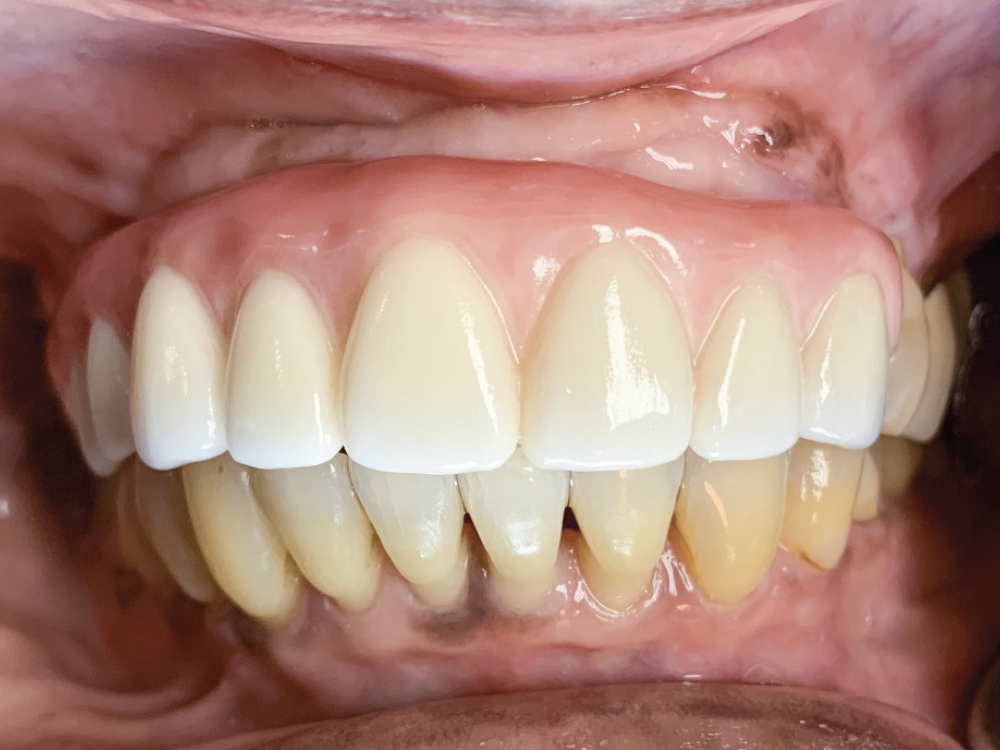

Figures 1a, 1b: At the initial consultation, the patient complained of her removable partial denture, desiring a fixed restoration that looked and felt more like natural teeth and would allow her to eat normally and smile without worrying about her prosthesis becoming loose. Because the patient’s remaining teeth were healthy and a conventional bridge was not an option, the patient agreed to receive four implants to support an FP-3 prosthesis, which would replace the missing teeth as well as the lost hard and soft tissue in the edentulous span.

Figure 12: At the final delivery appointment, the BruxZir Esthetic Partial-Arch Implant Prosthesis was seated. We checked the occlusion, contacts, lateral excursions and phonetics, and everything was exactly as expected. The patient was extremely happy with the lifelike esthetics of the restoration and enjoys the ability to eat and smile with confidence.